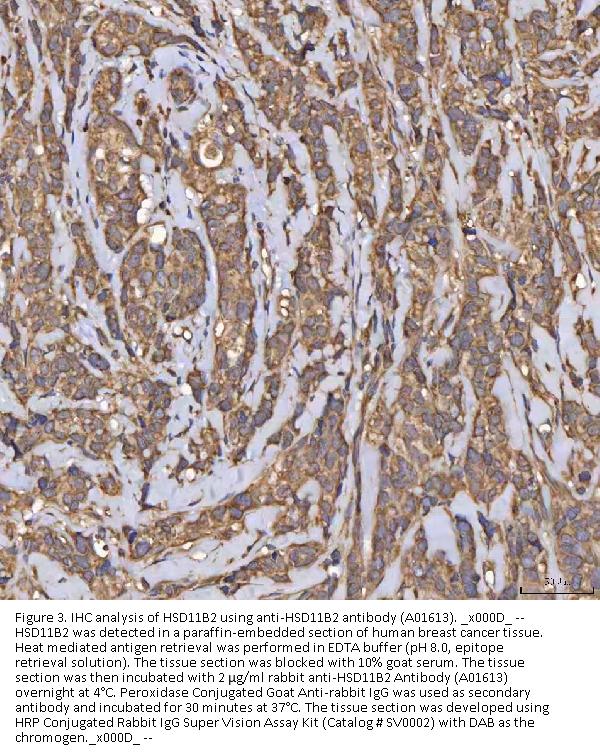

Immunohistochemistry(Paraffin-embedded Section), 2-5 μg/ml, Human

Boster Bio Anti-HSD11B2 Antibody Picoband® catalog # A01613. Tested in ELISA, Flow Cytometry, IF, IHC, WB applications. This antibody reacts with Human. The brand Picoband indicates this is a premium antibody that guarantees superior quality, high affinity, and strong signals with minimal background in Western blot applications. Only our best-performing antibodies are designated as Picoband, ensuring unmatched performance.